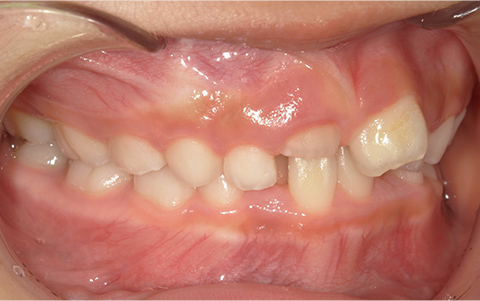

症例